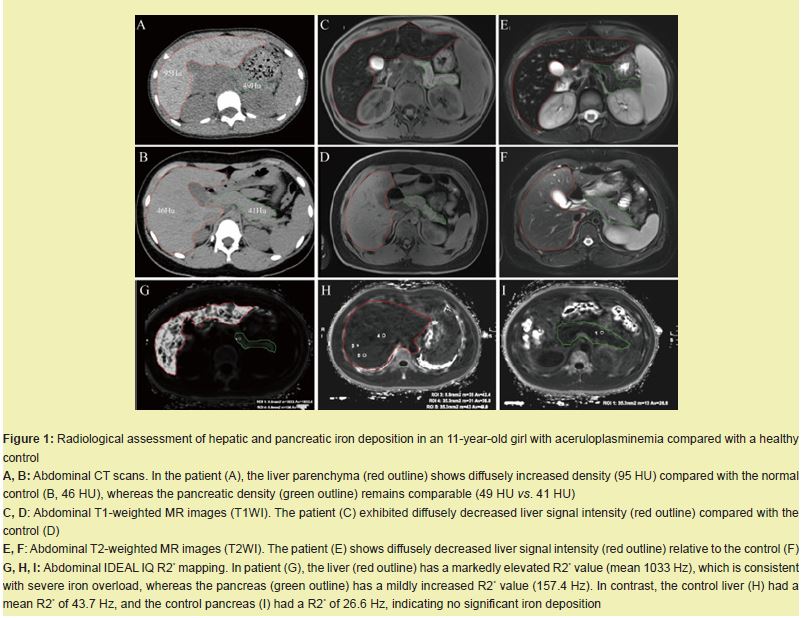

Iron accumulation in the cerebellar dentate nucleus on brain MRI

Brain MRI revealed bilaterally decreased signal intensity in the dentate nuclei on T1-weighted and T2-weighted images in the patient compared with the normal control Figure 2A–D. IDEAL-IQ R2* mapping revealed a markedly elevated R2* value of 121.4 Hz in the patient’s dentate nuclei, which was significantly greater than the control value of 25.7 Hz. The surrounding cerebellar tissue also showed mildly increased R2* (24.6 Hz vs. 19.0 Hz) Figure 2E,F. These findings indicate pathological iron accumulation in the cerebellar dentate nucleus.

We report an 11-year-old girl with genetically confirmed aceruloplasminemia—the youngest documented to date. She presented with refractory microcytic hypochromic anemia, growth delay, and mild cognitive impairment. Laboratory studies revealed paradoxically low serum iron and markedly elevated ferritin. Whole-exome sequencing revealed a homozygous splice-site variant, c.147-2A > G, in the Ceruloplasmin Gene (CP). Pedigree analysis revealed that the parents of the affected child are carriers of the mutation.CP has six structural domains with a three-copper catalytic center, one Ca+ binding site, and one Na+ binding site, all of which are essential for its oxidative function6 and protein stability.6,7 The c.147-2A > G variant disrupts the canonical acceptor splice site. Minigene assays revealed complete skipping of exon 2 Figure 3C, 3D. Structural modeling revealed that this deletion disrupts the trinuclear copper cluster bridging domains 1 and 6, eliminates both Na⁺- and Ca²⁺-binding sites Figure 3E-H, abolishes ferroxidase activity, and explains the undetectable serum ceruloplasmin (< 20 mg/L) and pronounced early iron loading Figure 1,2.